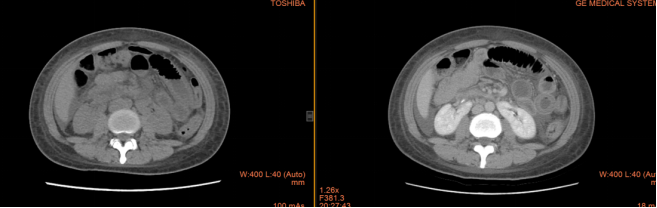

治疗前:

患者小范2月前因腹痛、呕吐在外科住院,诊断肠梗阻,予抗炎、通便治疗后症状好转出院,1月前再次出现反复腹痛、呕吐,CT平扫+增强提示肠壁水肿、增厚,呈“靶征”,胸腔、腹腔、盆腔大量积液。请风湿免疫结缔组织病科汤艳华主任会诊后,发现患者双手掌面多发痛性结节,完善相关免疫检查,发现抗核抗体阳性,dsDNA 阳性,补体下降,诊断系统性红斑狼疮、狼疮肠系膜血管炎转入风湿结缔组织病科。予大剂量激素冲击+免疫抑制剂+抗凝、抑酸等治疗后,症状完全缓解,并可以顺利进食。